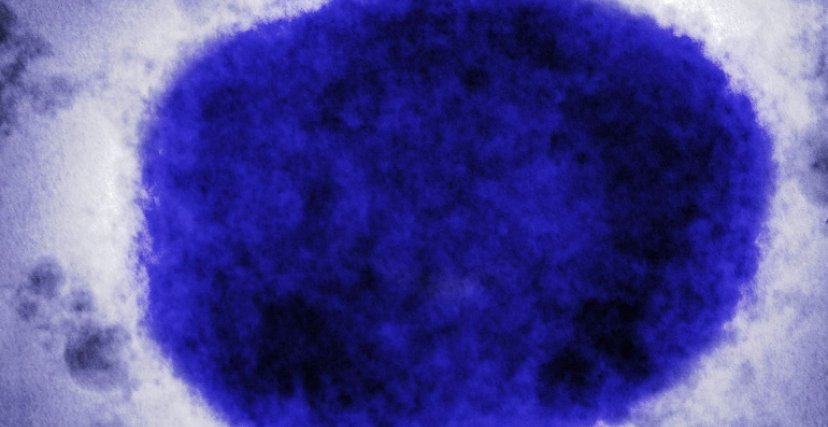

جوبا تعلن عن تفشي جدري القرود

وكانت وزارة الصحة في جنوب السودان قد أعلنت في وقت سابق عن تفشي جدري القرود في العاصمة جوبا، بولاية وسط الاستوائية، وذلك بعد تأكيد المختبر الوطني للصحة العامة لأول إصابة مؤكدة بالمرض في السادس من فبراير 2025.